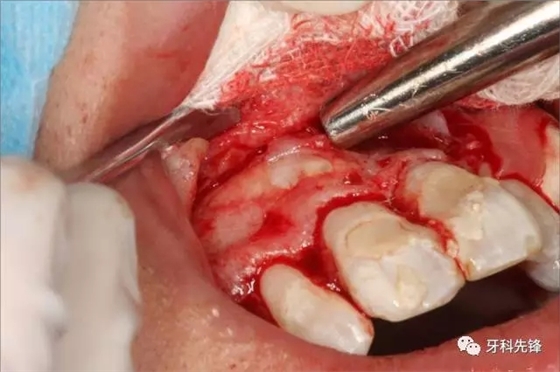

圖5.局麻下行唇側(cè)梯形切口

圖6.翻瓣、去骨、暴露13牙冠